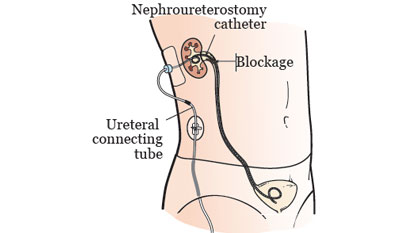

Nephrostomy Tube & Nephroureteral Stent Placement

Nephrostomy tube and nephroureteral stent placement are minimally invasive procedures used...